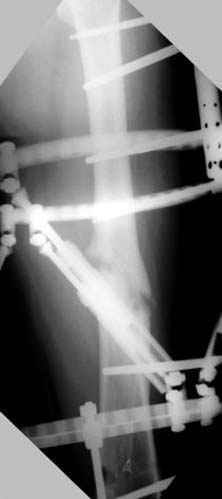

пластическая модель; и коррекция бедра аппаратом Илизарова.